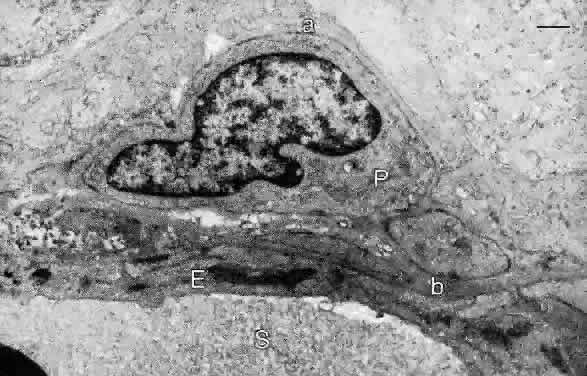

The arterial branches have smooth muscle walls and an endothelium but lack an internal elastic lamina. The branches of the central retinal vein have thin walls of smooth muscle and an endothelium, and the walls of the venules and capillaries contain mural cells (pericytes) enclosed within a basal lamina continuous with that of the endothelial cells (Fig. 19). The endothelial nuclei are oriented along the capillary axis and are long and pale; the mural cell nuclei are small and dense.

Fig. 19. Electron micrograph of retinal capillary wall demonstrating an endothelial cell (E) and its basal lamina (b). A pericyte (P) is surrounded by a basal lamina (a) on the side facing the retinal parenchyma. S, serum in capillary lumen. Bar = 1.0 μm. (Hogan MJ, Alvarado JA, Weddell JE: Histology of the Human Eye. Philadelphia: WB Saunders, 1971.)